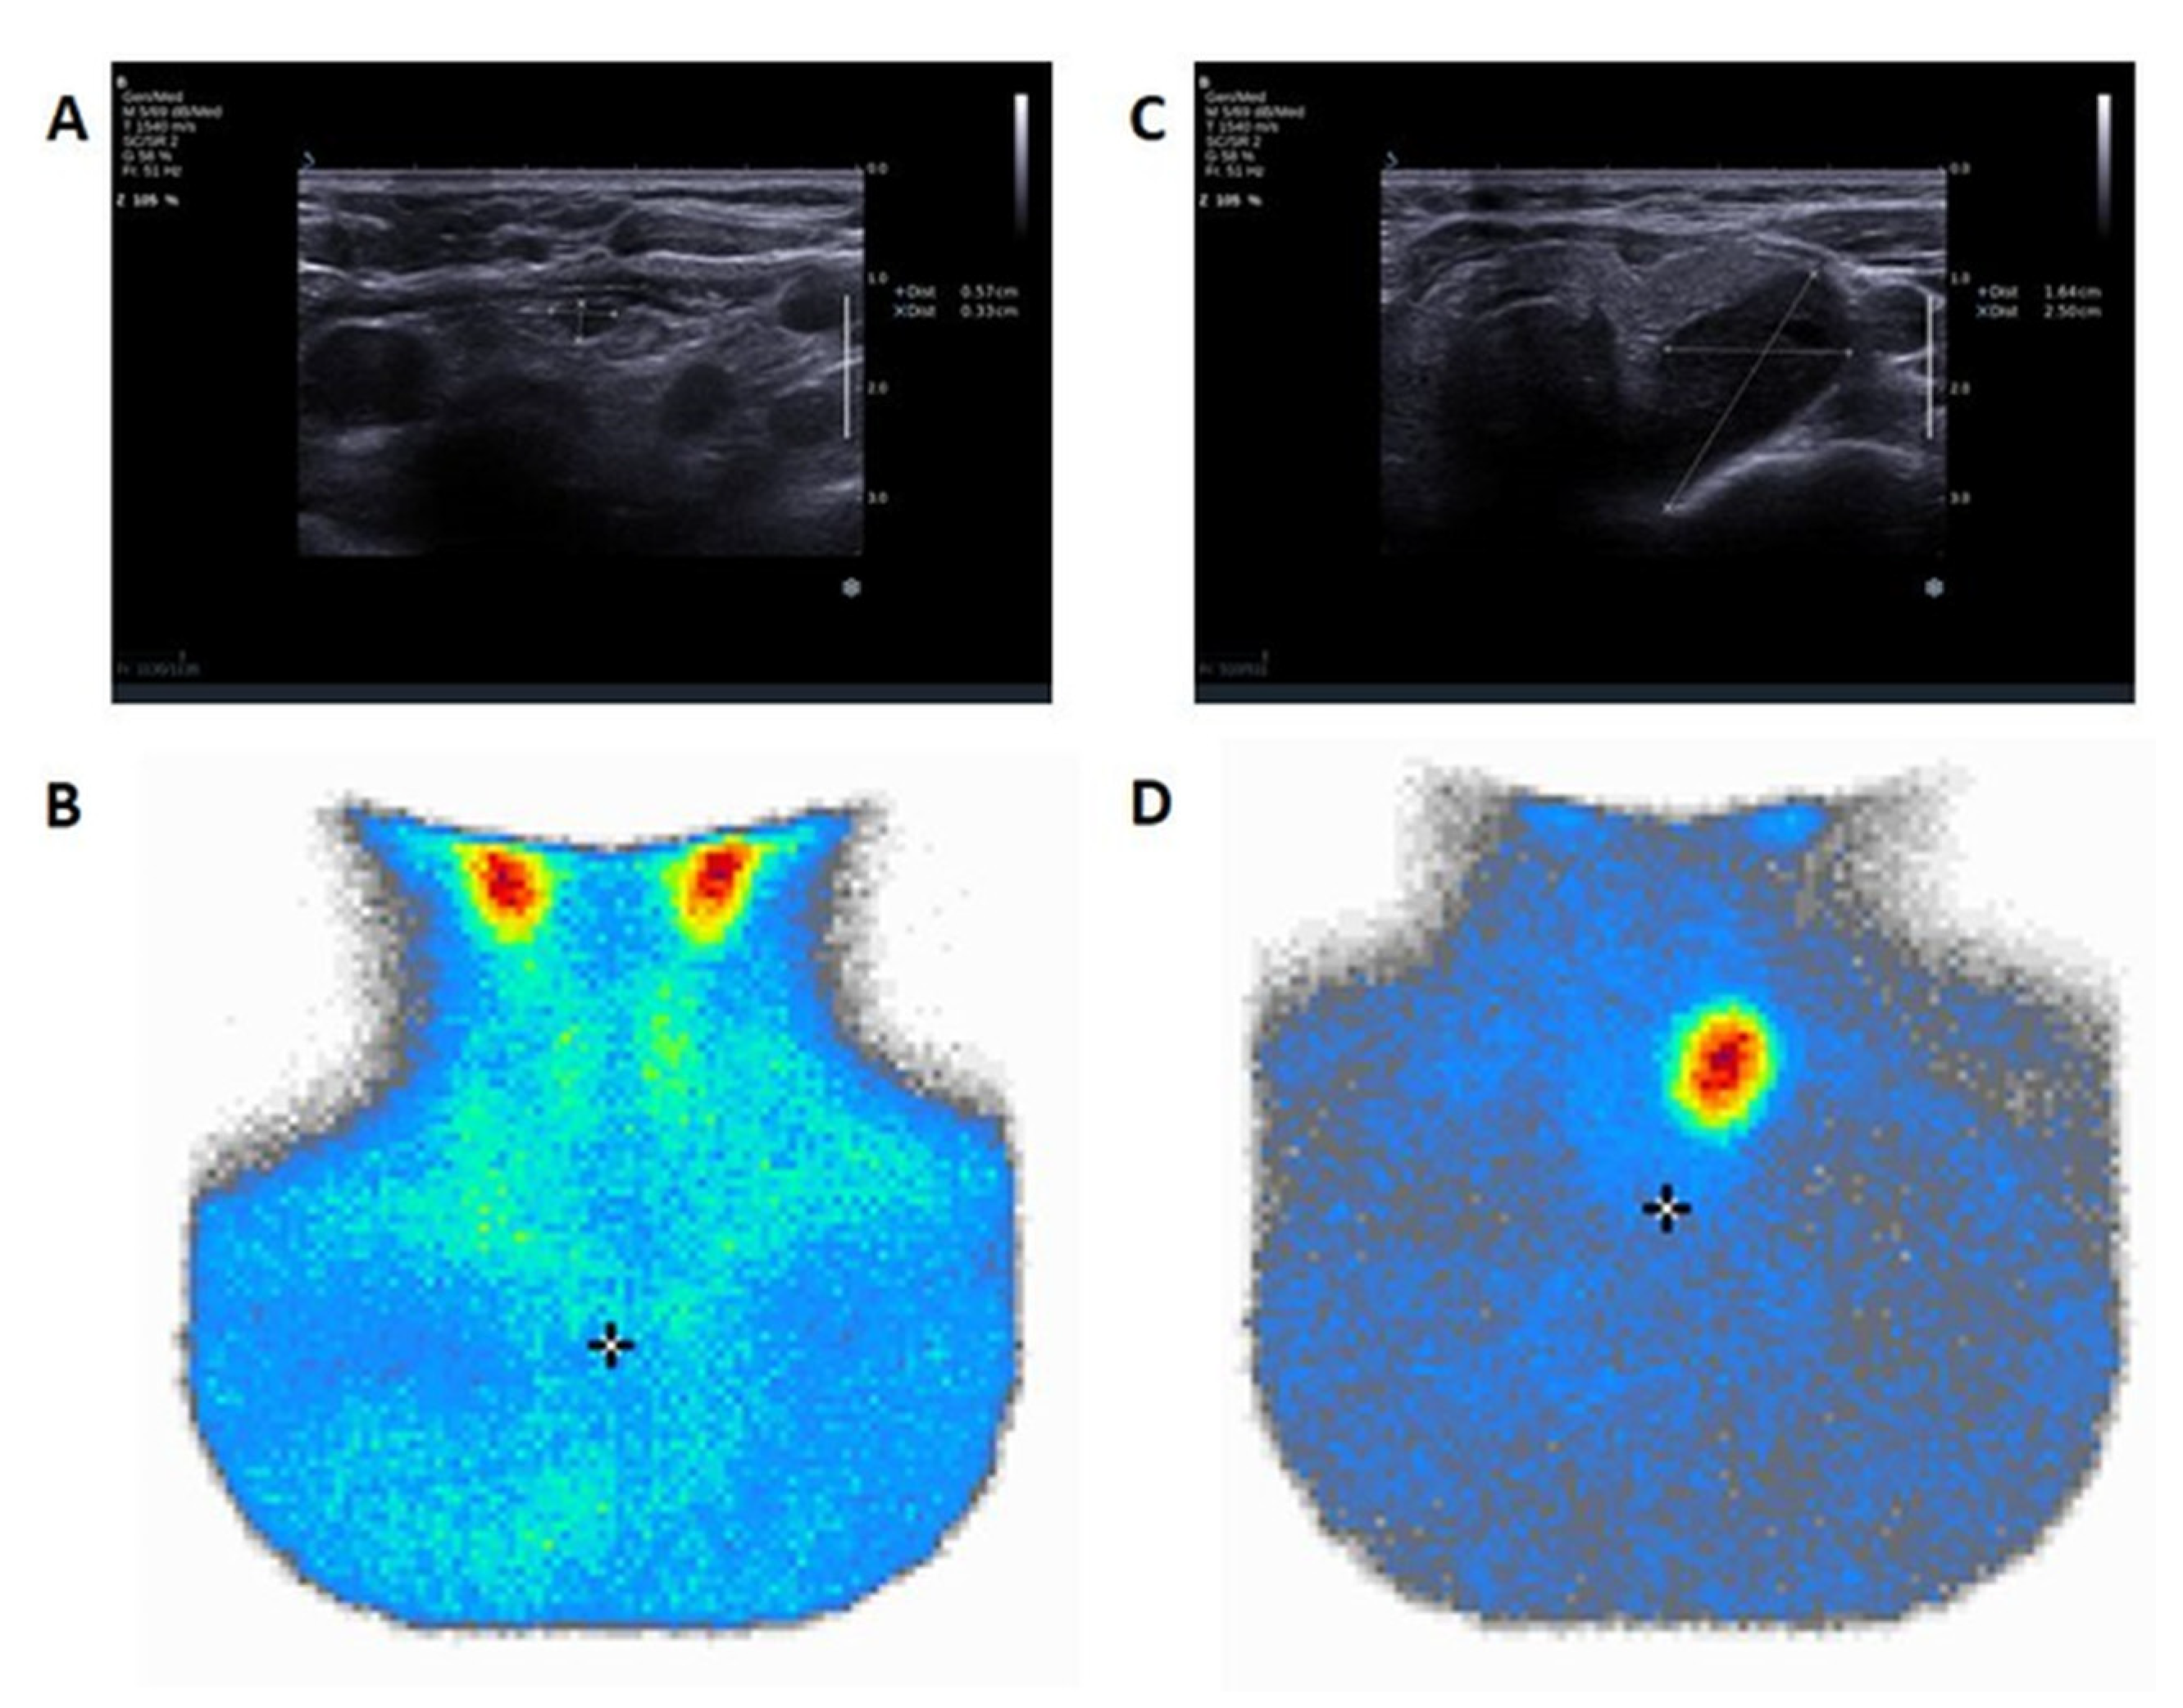

The results of PA localization obtained using ultrasound and PTHw were in agreement with the localisation suggested by MIBI in 77% (30/39) of cases. MIBI was unambiguously positive in 74% (29/39) of cases. Among patients with negative or inconclusive MIBI (multifocal or non-specific or negative uptake), 90% (9/10) had a positive PTHw result. In MIBI-positive patients, PTHw confirmed the presence of the PA location in 93% of cases (27/29). Within the group with positive PTHw, in 25% (9/36) of subjects, MIBI was inconclusive (eventually, in 8/9 cases, biochemical normalization was achieved after the resection of the PTHw positive lesion). Among patients with negative PTHw, two out of three had positive MIBI and underwent successful surgery (

Figure 1).